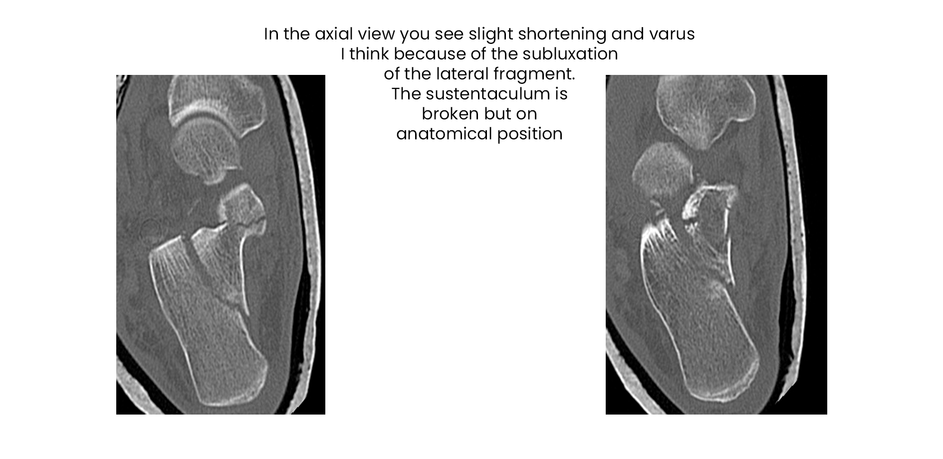

case 18ZJ, 23 years old, female, fall from horse, "atypical fracture" surgery after 2 days